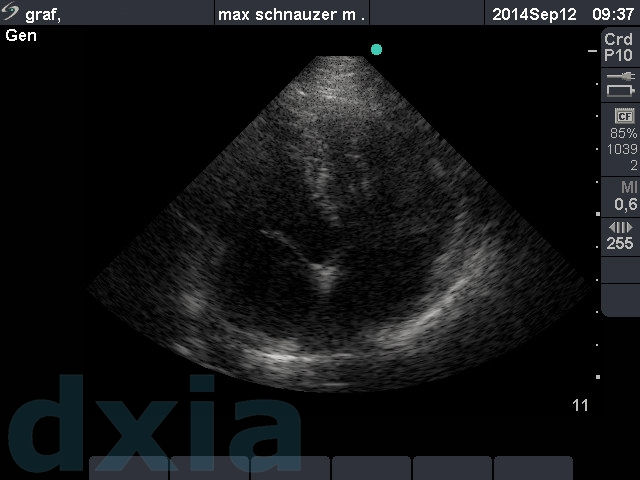

Imágenes obtenidas durante el estudio ecocardiográfico

apical craneal max

Apical craneal izquierdo 4 c

Válvulas normoimplantadas y sin alteraciones. No dilatación de cámaras.